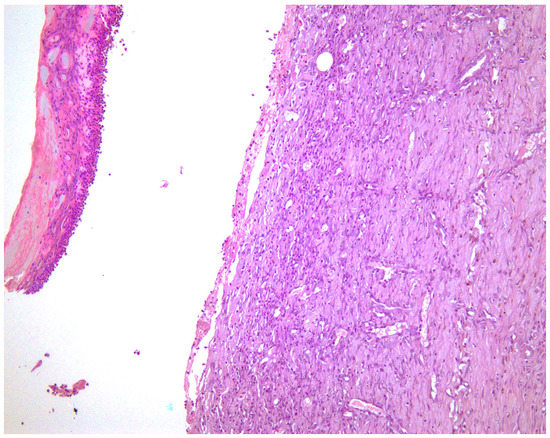

—fibrin clot,

—granulation tissue,

—adipose tissue.